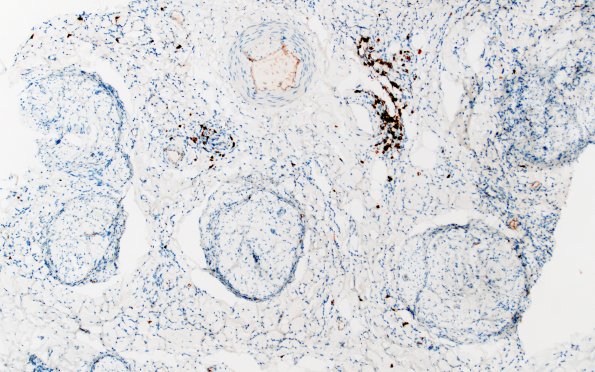

Washington University Experience | PERIPHERAL NEUROPATHY | 9B PERINEURITIS & PERINEURIAL PATHOLOGY | 1F2 Epineuritis & Perineuritis (Case 1) Immune checkpoint CD20 10X

The B cell population is limited and is largely confined to the perivascular region of the epineurium. (CD20 IHC)